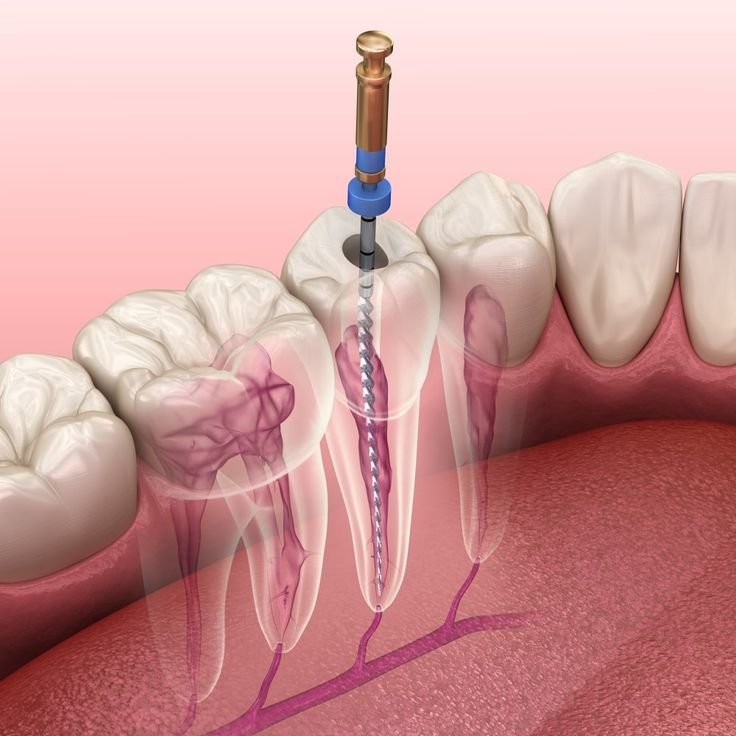

Endodonti

Kök kanal tedavisi (endodonti), diş pulpası (sinir + damar) iltihaplandığında veya öldüğünde kök kanallarını temizleme,

Acil pulpa tedavisi, şiddetli diş ağrısı, travma, kırık veya apse nedeniyle diş pulpası (sinir + damar) acilen kısmi veya tam

Kök kanallarının tekrar tedavisi (endodontik retreatment), önceki kanal tedavisinin başarısız olduğu (enfeksiyon, sızıntı, kırık alet)